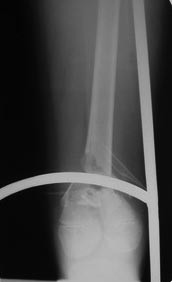

У неё переломы обеих седалищных костей без смещения значительного.

Переломы оскольчатые обеих бёдер в н/3, открытые. Раны ушиты в отличном

состоянии.

На одном бедре межмыщелковый перелом и там мыщелки немного разъехались.

Голень там тоже сломана в н/3 обе кости. Снимок голени в боковой

проекции сделан не был.